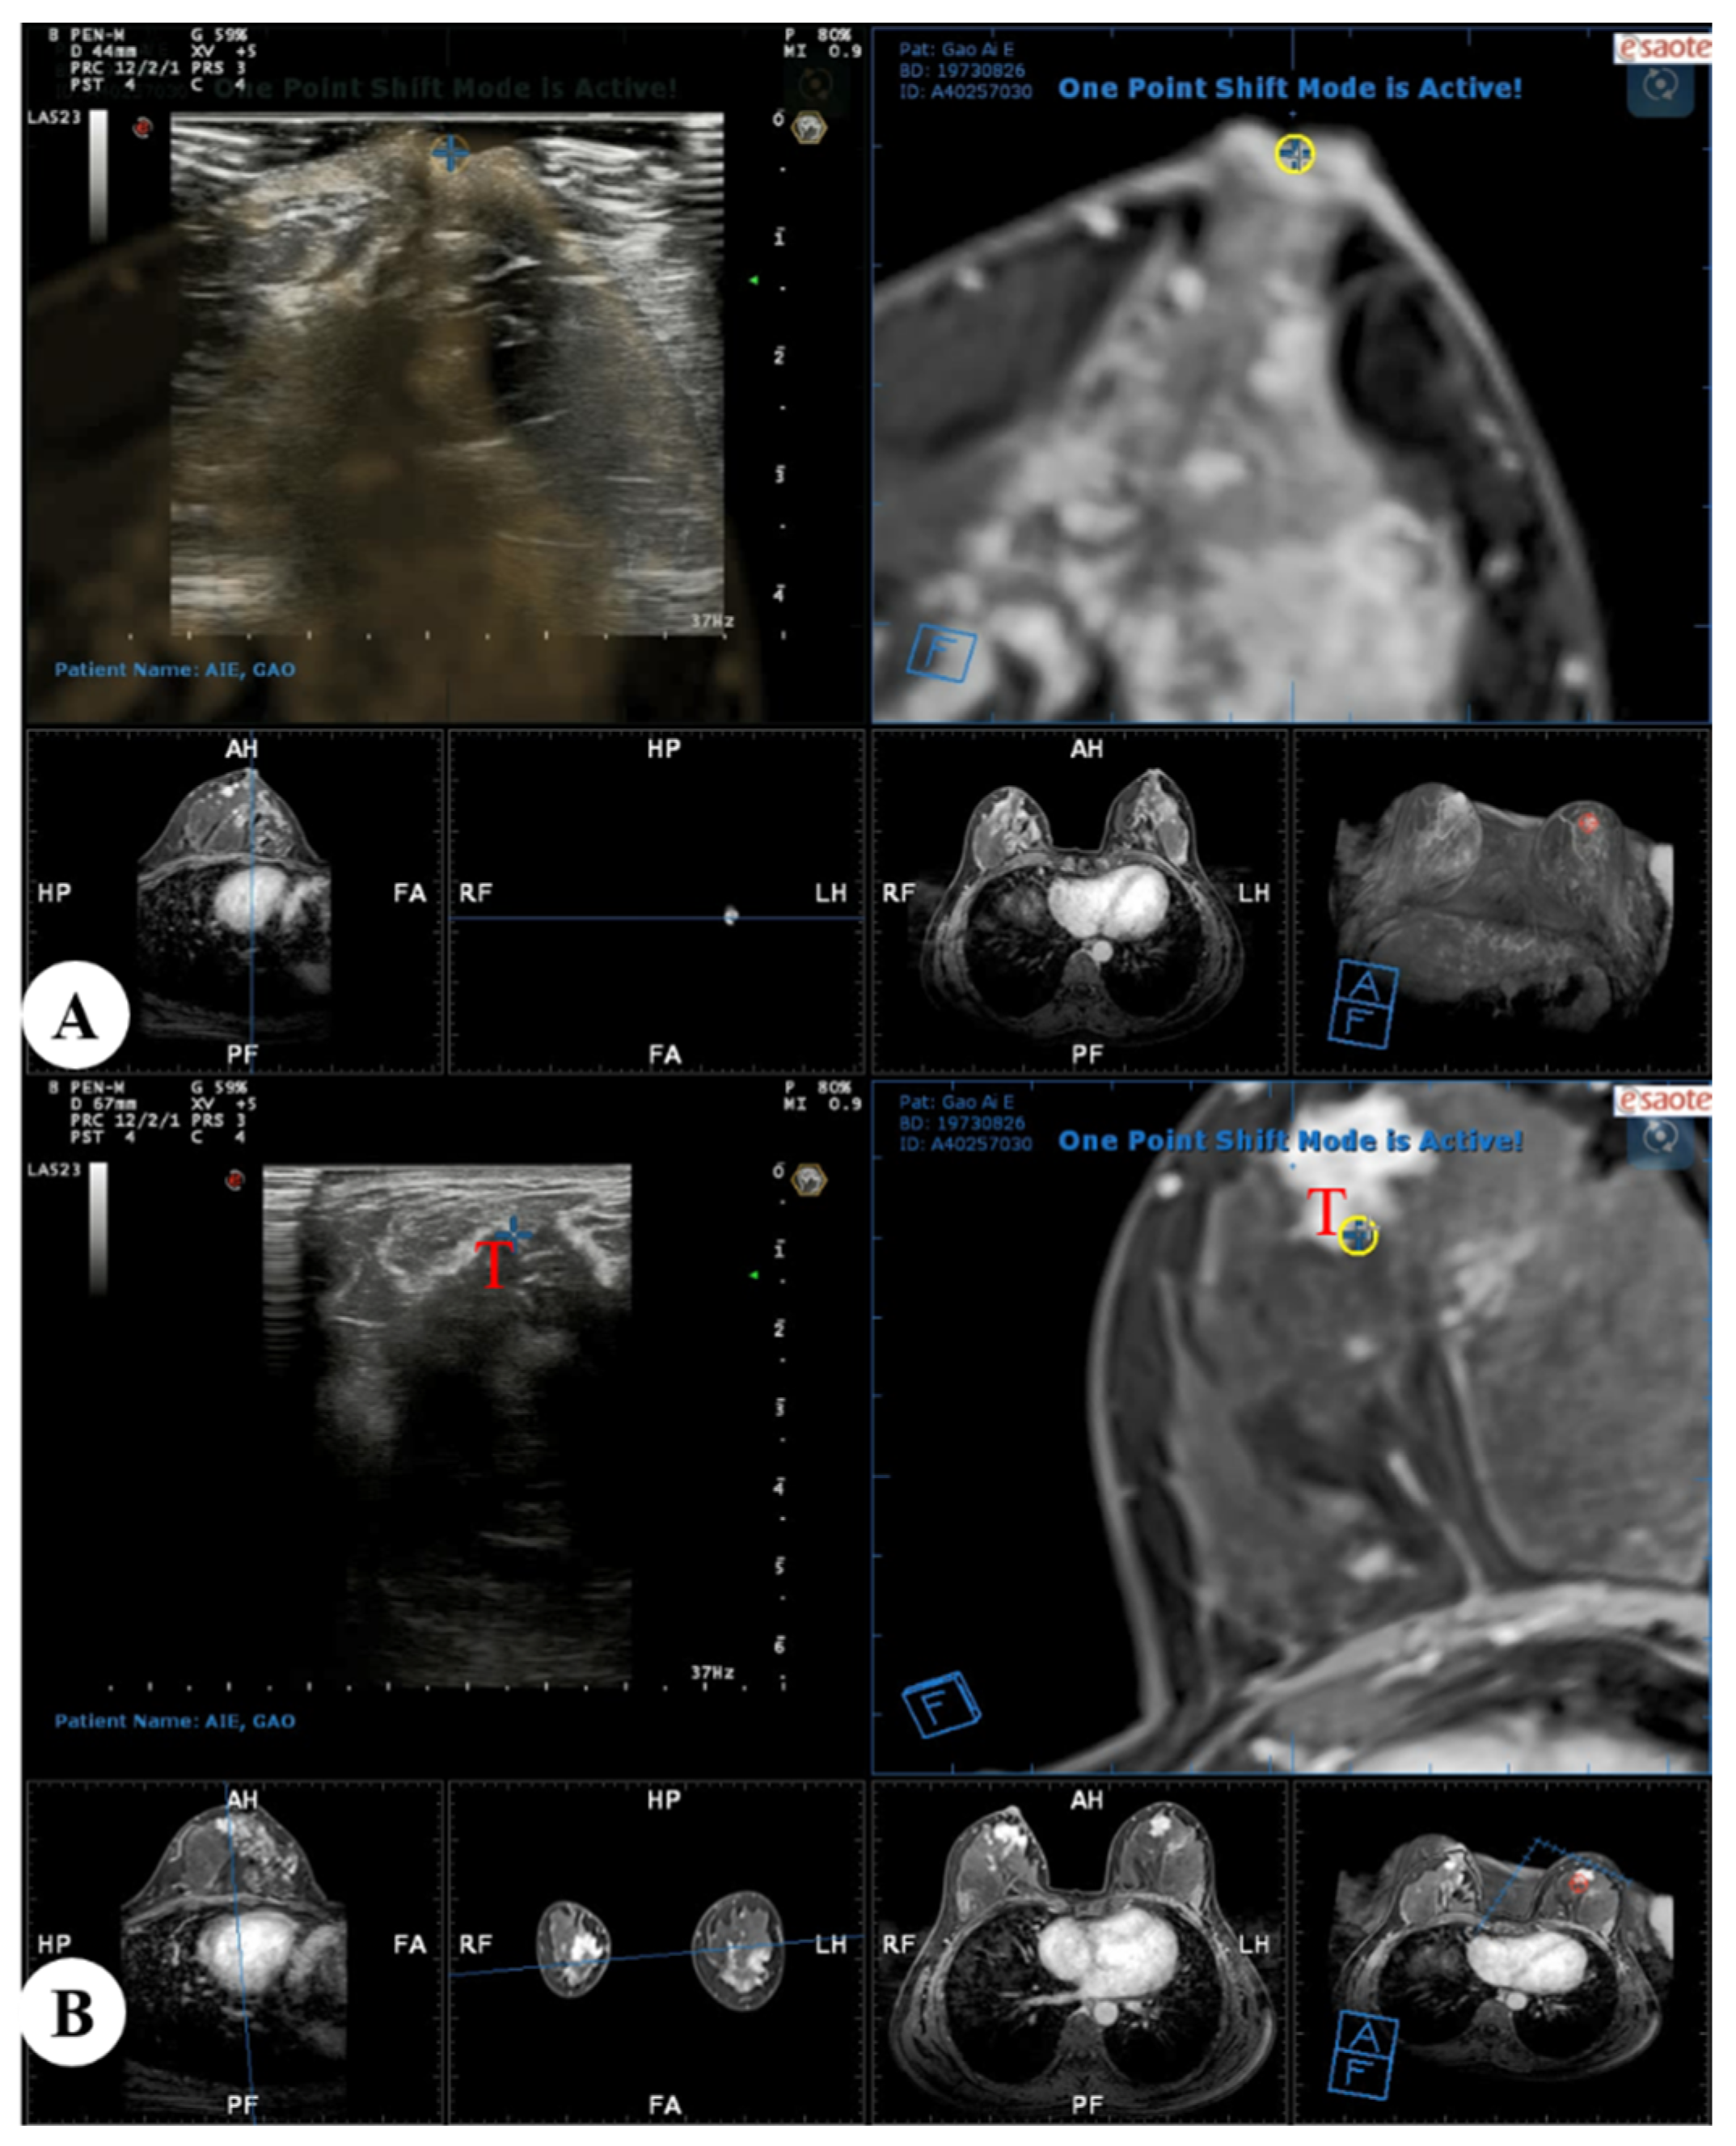

Figure 3.

Real-time US with virtual navigation was performed in the prone position: (A) A co-registration process between real-time US and MRI-MPR images was performed with the nipple as a reference point, and the contour of the breast and internal anatomic landmarks were aligned; (B) Search and localization using real-time US with virtual navigation of the corresponding suspected enhanced lesion (T, target) identified on MRI alone. US = ultrasound; MRI = magnetic resonance imaging; MPR = multiplanar reconstruction.